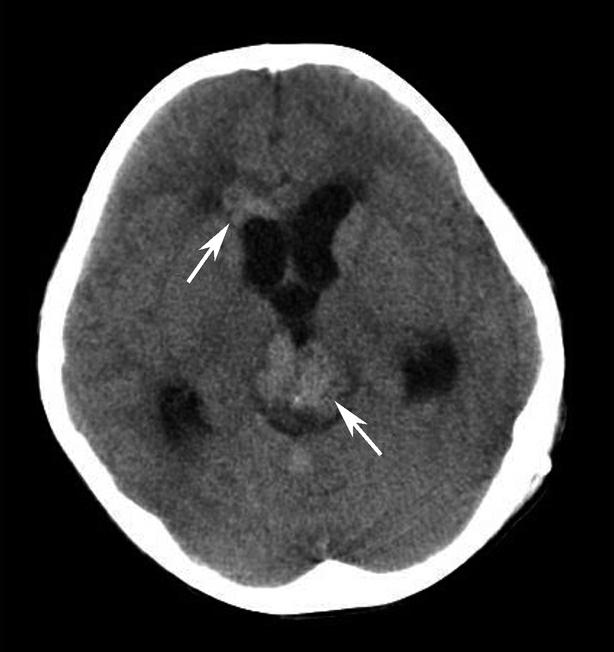

图1-2-87 脑挫裂伤并脑室内积血

右侧颞叶(白箭)、左侧基底节区(白箭头)大片状高、低混杂密度影。左侧侧脑室后角积血(黑箭)